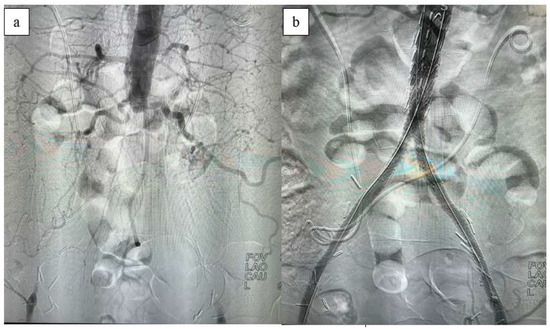

Figure 2. Intraoperative (a) and post-CERAB (b) aortography.

When the iliac lesion is complete, brachial access is also utilized for aortography. If the brachial artery diameter is adequate, a sheath is placed in the antecubital fossa using the Seldinger technique under ultrasound guidance. For sheaths larger than 6 Fr, access to the brachial artery is achieved via the cut-down technique. The lesion is crossed antegradely through the brachial access, and the guidewire is captured with a snare from the femoral artery to continue the procedure. If the common femoral artery is entirely occluded with no discernible lumen, an alternative approach involves creating retrograde access by initially performing an endarterectomy (Figure 2).

Following control angiography, the sheaths are removed from the common femoral arteries, and hemostasis is achieved with purse-string sutures. If the common femoral artery shows inadequate lumen due to extensive calcification, femoral endarterectomy and patchplasty are added to the procedure. After the procedure, patients are extubated, monitored in the intensive care unit for 24 h, and administered low-molecular-weight heparin in addition to dual antiplatelet therapy due to limited mobilization during hospitalization.